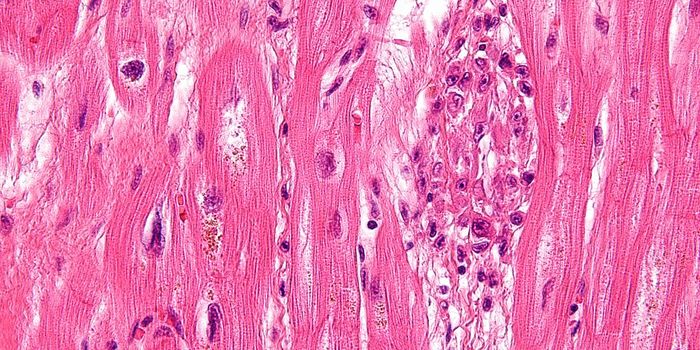

FEB 09, 2024CancerHistopathology describes the process of examining pieces of tissue using a microscope. Light microscopic (LM) exam ...